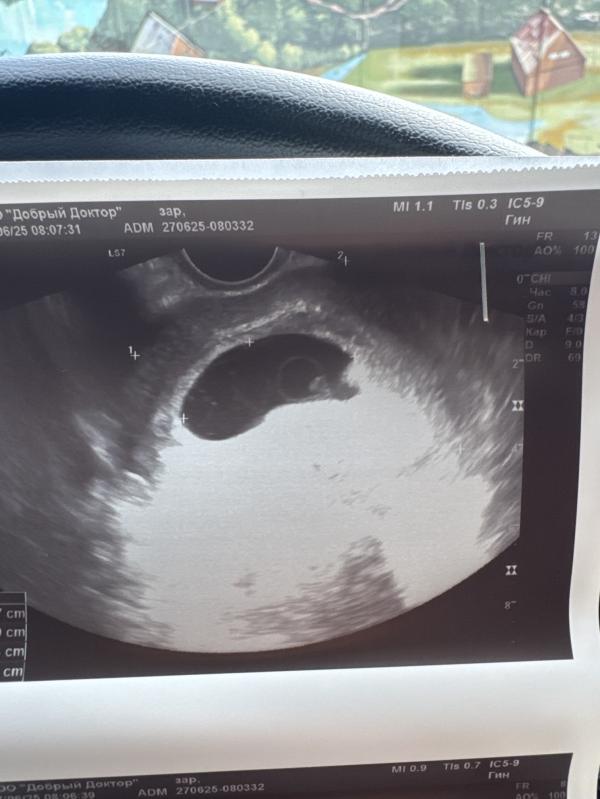

Сегодня ровно 8 недель !до этого была на узи в 6.5 было только ПЯ и желтое тело, сегодня на узи сказали совсем маленькая точка есть , сердцебиения нет ,по сроку уже должен быть эмбрион 10мм, а у меня КТР 3 ммсердцебиения нет. И там просто точка

Сказали ждать смысла нет ,замершая ,что думаете ? #первыйпост

Меня смущает что КТР 3 мм на таком сроке - 8 недель ,врач сказала не развивается ,эмбрион совсем точка 😢ну и плюсом что нет сердцебиения